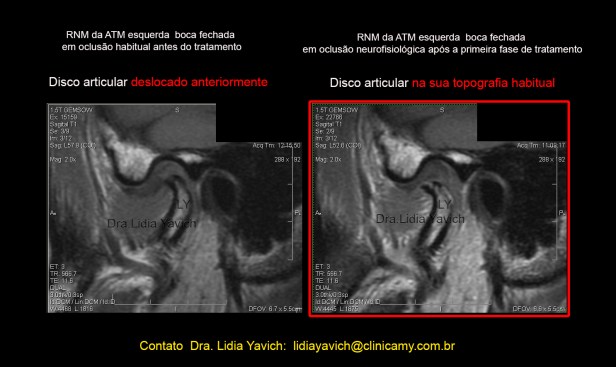

RNM: Ressonância Nuclear Magnética do paciente. Corte selecionado.

1 corte sagital da ATM ESQUERDA em boca fechada antes do tratamento. Deslocamento redutivel do disco articular.

2 -A mesma imagem com realce de cores.

3 -corte sagital da ATM ESQUERDA em boca aberta antes do tratamento.

4– A mesma imagem com realce de cores.  RNM: Ressonância Nuclear Magnética do paciente. Corte selecionado. Corte sagital da ATM DIREITA em boca fechada antes do tratamento.

Corte sagital externo da ATM esquerda em boca fechada antes do tratamento mostrando o DESLOCAMENTO DO DISCO ARTICULAR e a RECAPTURA DO DISCO ARTICULAR após o tratamento.

Controle comparativo da segunda ressonância nuclear magnética após a primeira fase do tratamento. Serão postadas as imagens da ATM esquerda, que apresentava o deslocamento do disco articular.

Corte sagital externo da ATM esquerda em boca fechada antes do tratamento mostrando o DESLOCAMENTO DO DISCO ARTICULAR e a RECAPTURA DO DISCO ARTICULAR após o tratamento.

Corte sagital interno da ATM esquerda em boca fechada antes do tratamento mostrando o DESLOCAMENTO DO DISCO ARTICULAR e a RECAPTURA DO DISCO ARTICULAR após o tratamento.

Corte sagital interno da ATM esquerda em boca fechada antes do tratamento mostrando o DESLOCAMENTO DO DISCO ARTICULAR e a RECAPTURA DO DISCO ARTICULAR após o tratamento.